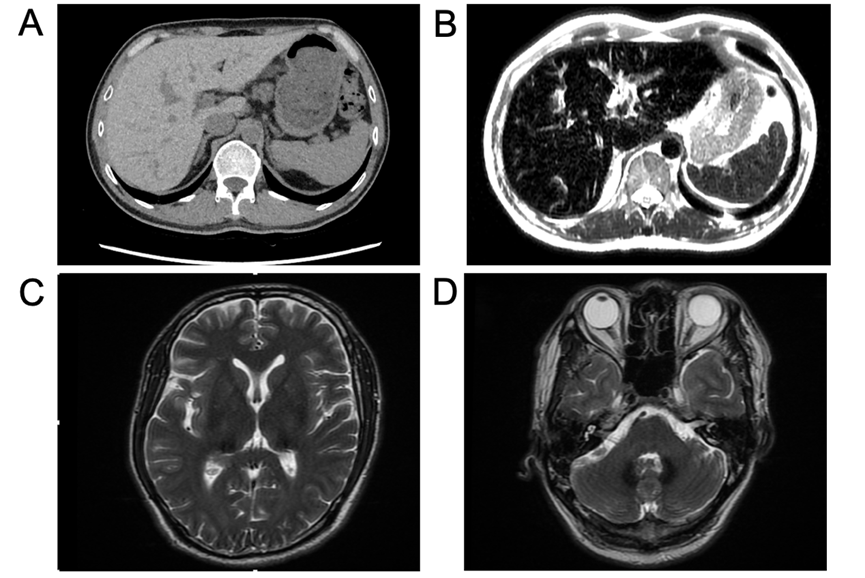

患者45岁男性,因“失眠20个月,腹胀不适2个月”入院。用药史及家族史无特殊。20个月前患者因“睡眠差、失眠”在当地医院诊断为“糖尿病”,发现血清铁蛋白2233 ng/mL,铜蓝蛋白< 0.024 g/L,肝脏CT值85.62 HU(图A)。2月前出现腹胀不适,查铁蛋白19710 ng/mL,ALT 301 U/L,AST 190 U/L,当地医院给予中药及护肝药物治疗,肝功能有所好转,病因未明,入我院行进一步诊治。

查体:胸前毛细血管扩张(+),无肝掌及蜘蛛痣。实验室检:血红蛋白118 g/L,白细胞和血小板计数正常,网织红细胞3.09%。肝功能及凝血功能基本正常,血糖 15.27 mmol/L,总胆固醇5.19 mmol/L,血清铁14.4 μmol/L,转铁蛋白饱和度45.1%,糖化血红蛋白6.2%。肝炎病毒标志物、自身免疫性抗体检查均为阴性。彩超肝胆脾胰未见明显异常。眼科:视网膜平伏,未见出血或渗出。腹部MRI-T2相显示肝脏、胰腺及脾脏明显低信号(图B)。头颅MRI显示双侧丘脑、基底节区和齿状核存在对称性斑片状短T2信号(图C、D)。骨髓穿刺涂片、组织病理学活检和染色体核型分析均未发现异常。肝脏穿刺活检显示慢性轻度炎症性肝损伤(G1S1)改变,肝细胞和库普弗细胞内有显著的含铁血黄素沉积,普鲁士蓝染色呈阳性(图E-H)。

3、影像学检查获铁沉积关键证据:腹部CT与MRI清晰显示肝脏、胰腺等器官重度铁过载的特征,而脾脏铁沉积轻;头颅MRI发现双侧丘脑、基底节区等关键脑区的对称性铁沉积,这是ACP重要的临床表现。